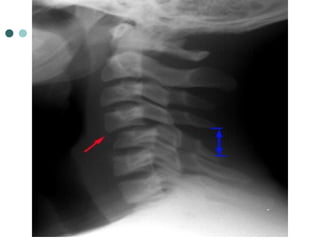

ANTERIOR SUBLUXATION

 Disruption of the posterior

ligamentous complex resulting from

hyperflexion

 Difficult to diagnose because muscle

spasm may result in similar findings

on the radiograph. May be stable

initially, but it associates with 20%-

50% delayed instability

 Flexion and extension views are

helpful in further evaluation.

 Signs:

 Loss of normal cervical lordosis

 Anterior displacement of the

vertebral body

 Fanning of the interspinous

distance

ANTERIOR SUBLUXATION  Disruptionof the posterior ligamentous complex resulting from hyperflexion  Difficult to diagnose because muscle spasm may result in similar findings on the radiograph. May be stable initially, but it associates with 20%- 50% delayed instability  Flexion and extension views are helpful in further evaluation.  Signs:  Loss of normal cervical lordosis  Anterior displacement of the vertebral body  Fanning of the interspinous distance